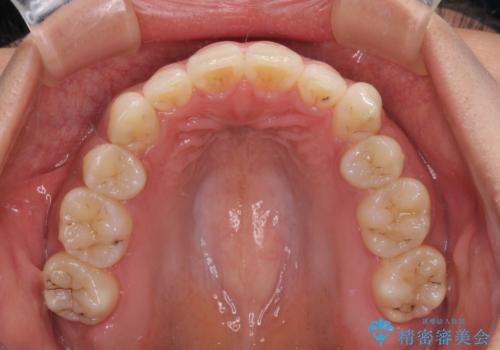

- 以前の矯正治療の後戻りにより、上下の前歯がでこぼこになってしまったことを気にして来院された患者様です。

口元がこれ以上突出することなく前歯の叢生が改善できるよう、歯と歯の間を削ってスペースを獲得し、インビザラインを用いて整えていくこととしました。

目安の装着時間である1日22時間をしっかりと実践してくださり、半年強という短期間で治療を終えることができました。